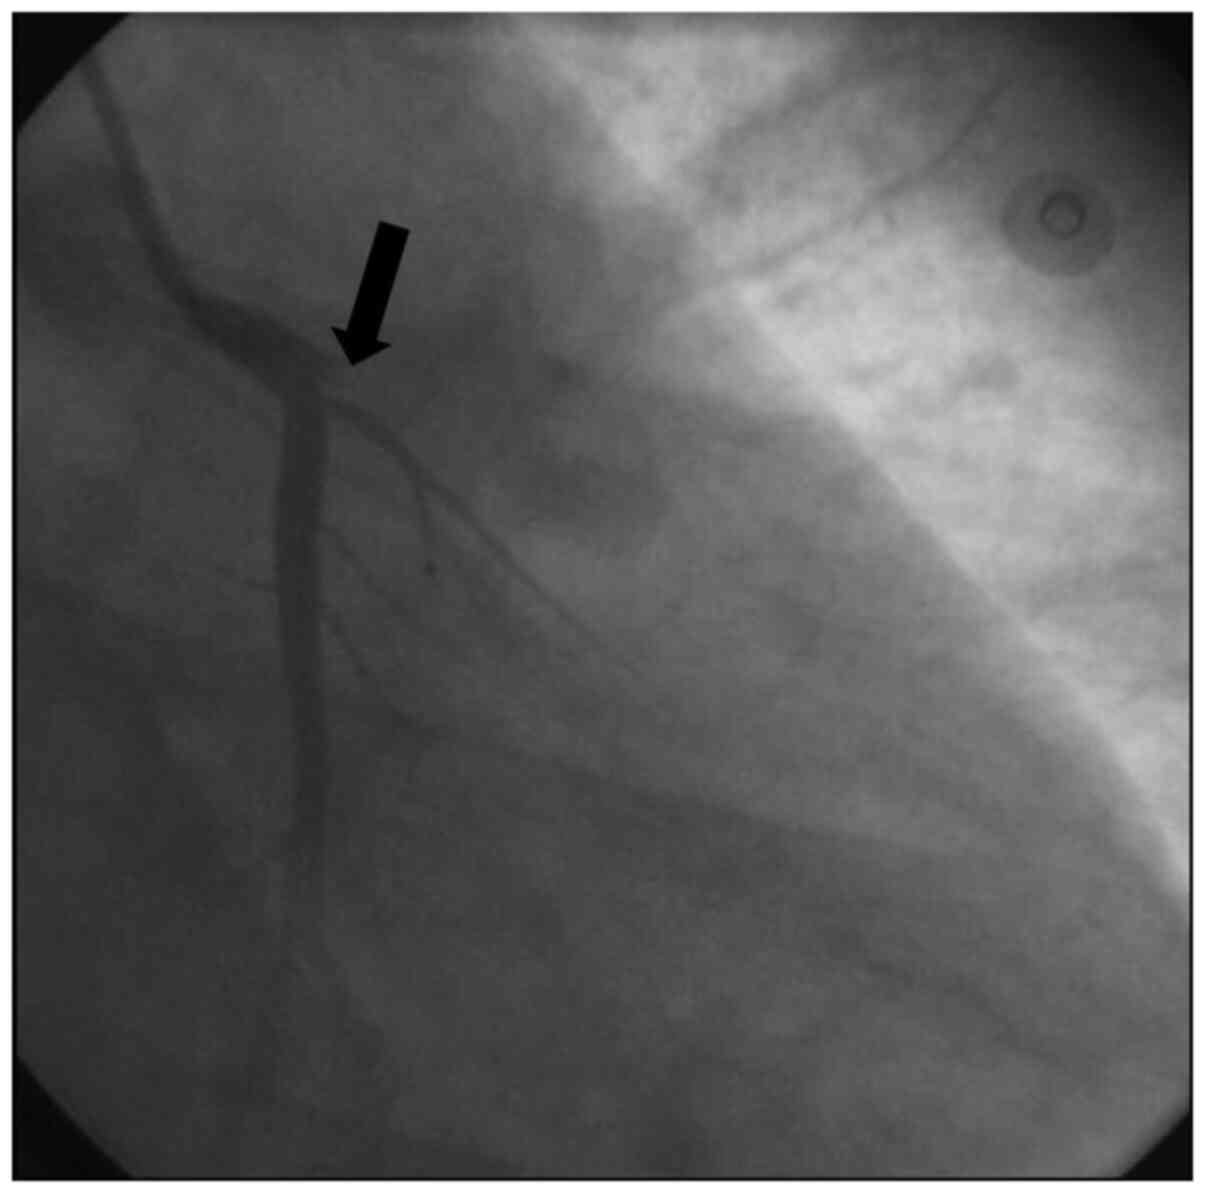

Urgent cardiac catheterization was performed 1 h after admission to the CCU, and total occlusion of the ostium of the left anterior descending artery by large thrombus was observed (Fig. 1). Successful recanalization was performed with a bare metal stent (BMS) (3.5x23 mm), and thrombolysis in myocardial infarction 2 flow was established. The patient was then administered tirofiban using percutaneous coronary intervention (PCI). The left circumflex artery was normal; however, notably, the right coronary artery (RCA) was affected: The pre-bifurcation was totally occluded by an embolized thrombus (Fig. 2). This may explain the changes in ECG observed in the CCU. Successful recanalization was performed with a BMS (3x18 mm). An intra-aortic balloon pump was inserted, and the patient was administered a small dose (5 µg/kg/min) of the vasopressor dopamine for 2 days.

Figure 1

Angiogram of the left coronary branches. The black arrow indicates total ostial occlusion of the left anterior descending artery by large thrombus.

Notably, in the present case, the patient may have suffered from both atherogenic (Fig. 1) and thrombotic (Fig. 2) coronary blockages. However, as it was not possible to examine the patient prior to hospital admission, it is unknown if the use of AASs caused the left atherosclerotic coronary lesion or, alternatively, if this use exacerbated a pre-existing lesion. Conversely, there was no clear evidence of an intra-ventricular thrombus, which may have explained the embolic thrombus in the right coronary artery. The documented evidence of the ability of AASs to increase blood thrombosis (5) may explain this event. In addition, although the vasospastic mechanism is less established as a factor in AASs-based AMI (15,16), it may possibly intensify the atherogenic or the thrombotic mechanisms of AMI in AASs users. In concordance with these data, AAS abuse has been identified to induce vascular and endothelial dysfunctions (17,18). Therefore, vasospastic agents were added to the pharmacological regimen of the patient in the present report. In addition, the ability of chronic AASs use to cause arrhythmias (19,20) may lead to spontaneous formation of small thrombotic embolisms, which in turn, may be transported toward the coronary arteries and cause significant blockages. Notably, the AMI itself in chronic AASs users may also cause disruption to the autonomic nervous supply of the heart, which may predispose these individuals to spontaneous arrhythmias (5,21). In turn, this may cause a thrombotic event within the ventricles, which may translocate to the coronary arteries and cause an embolism.